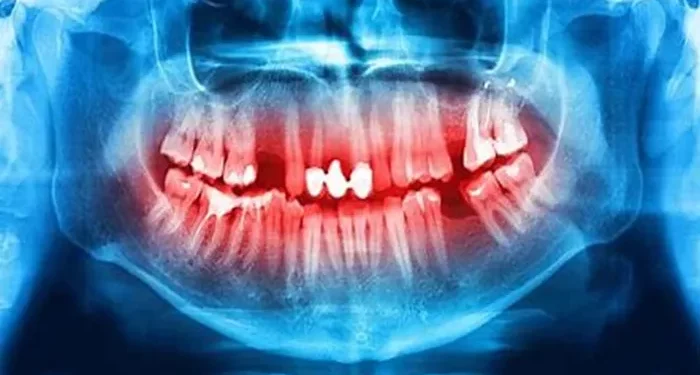

- Visual examination

- Dental explorer check

- Bitewing X-rays

- Laser detection devices

- Caries risk assessment